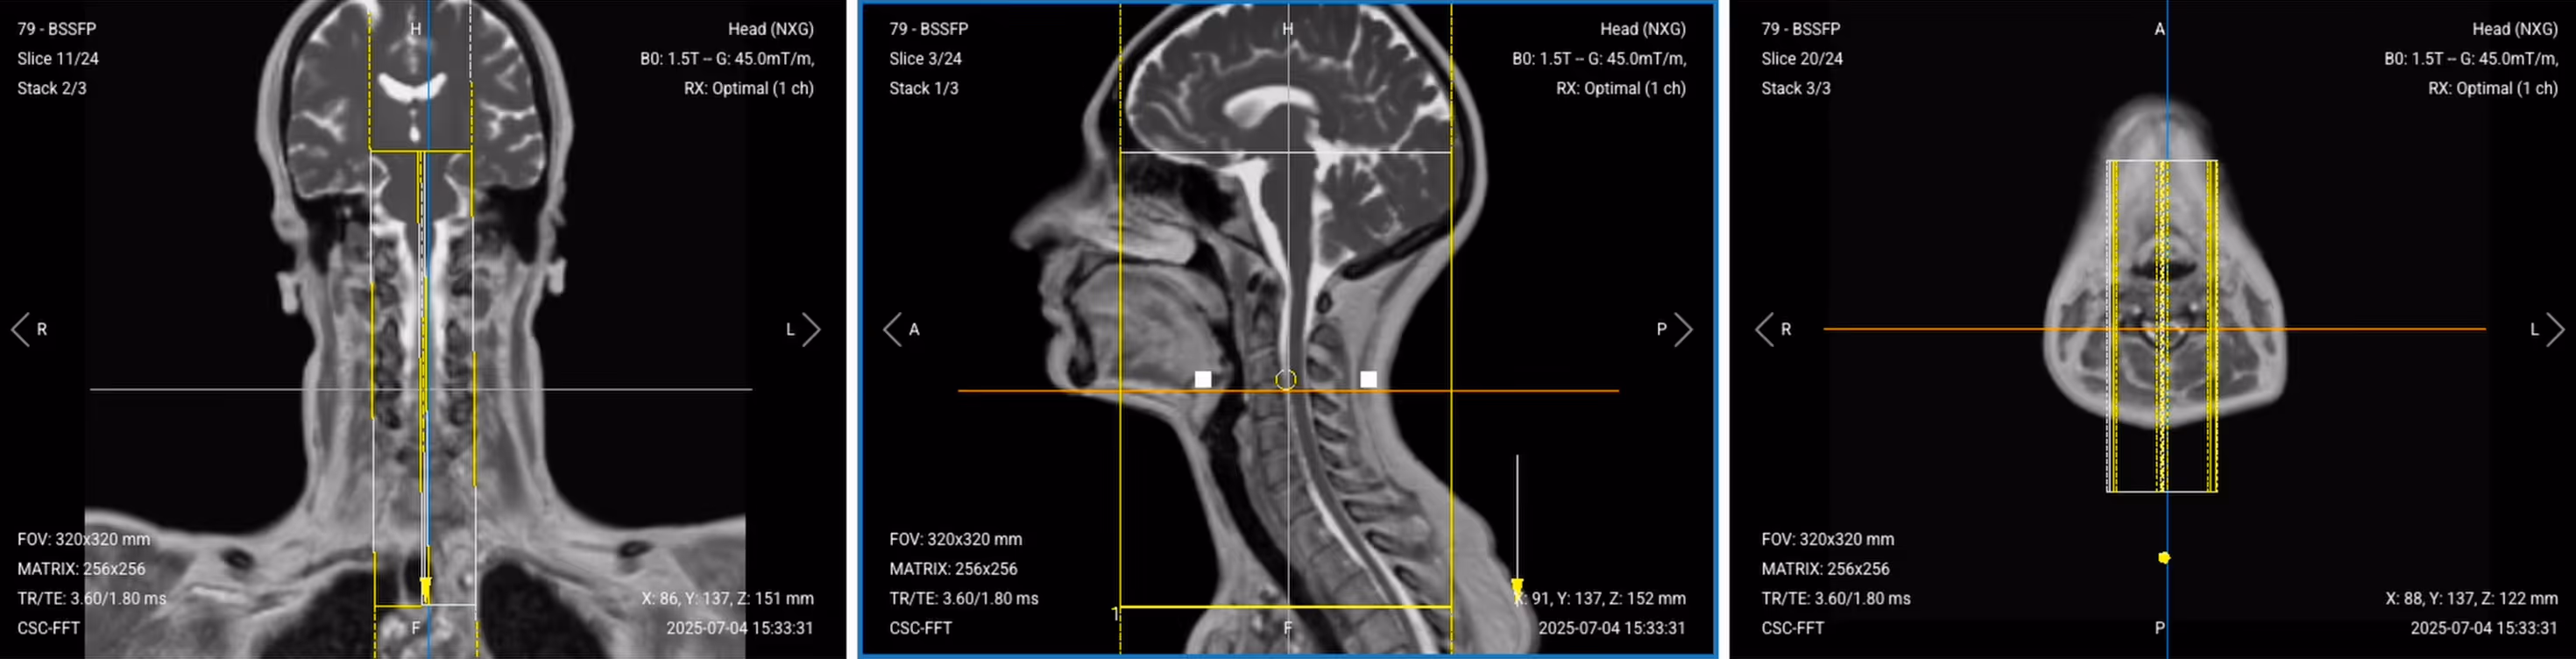

4. Planning Coronal T2 TSE

✅ Correct Planning:

Correct Planning of Coronal T2 TSE

Planning Instructions:

• Use the spinal cord as your anatomical reference.

• Align the slices as follows:

• Sagittal localizer: Align slices parallel to the spine and center them.

• Axial localizer: Slices should be perpendicular to the midline that passes through the vertebral body to the posterior processes.

• Use appropriate geometry parameters:

• Slice number: Enough to cover from anterior cervical spine to posterior (typically 15–25 slices).

• Slice thickness: 3 mm, consistent with sagittal sequences.

• Slice gap: 0.3 mm, maintains consistency with other sequences.

• Set the fold-over direction (phase encoding) to foot-to-head (FH) to avoid flow artifacts, same as sagittal sequences.

Coronal T2 TSE of the Cervical Spine – Correct Image Example:

Coronal T2 TSE of the Cervical Spine – Correct Image Exampl

Things to Look for in Coronal T2:

• Neural foramina should be open and symmetric.

• Look for lateral disc herniations or foraminal stenosis.

• Assess spinal cord alignment and any lateral compression.